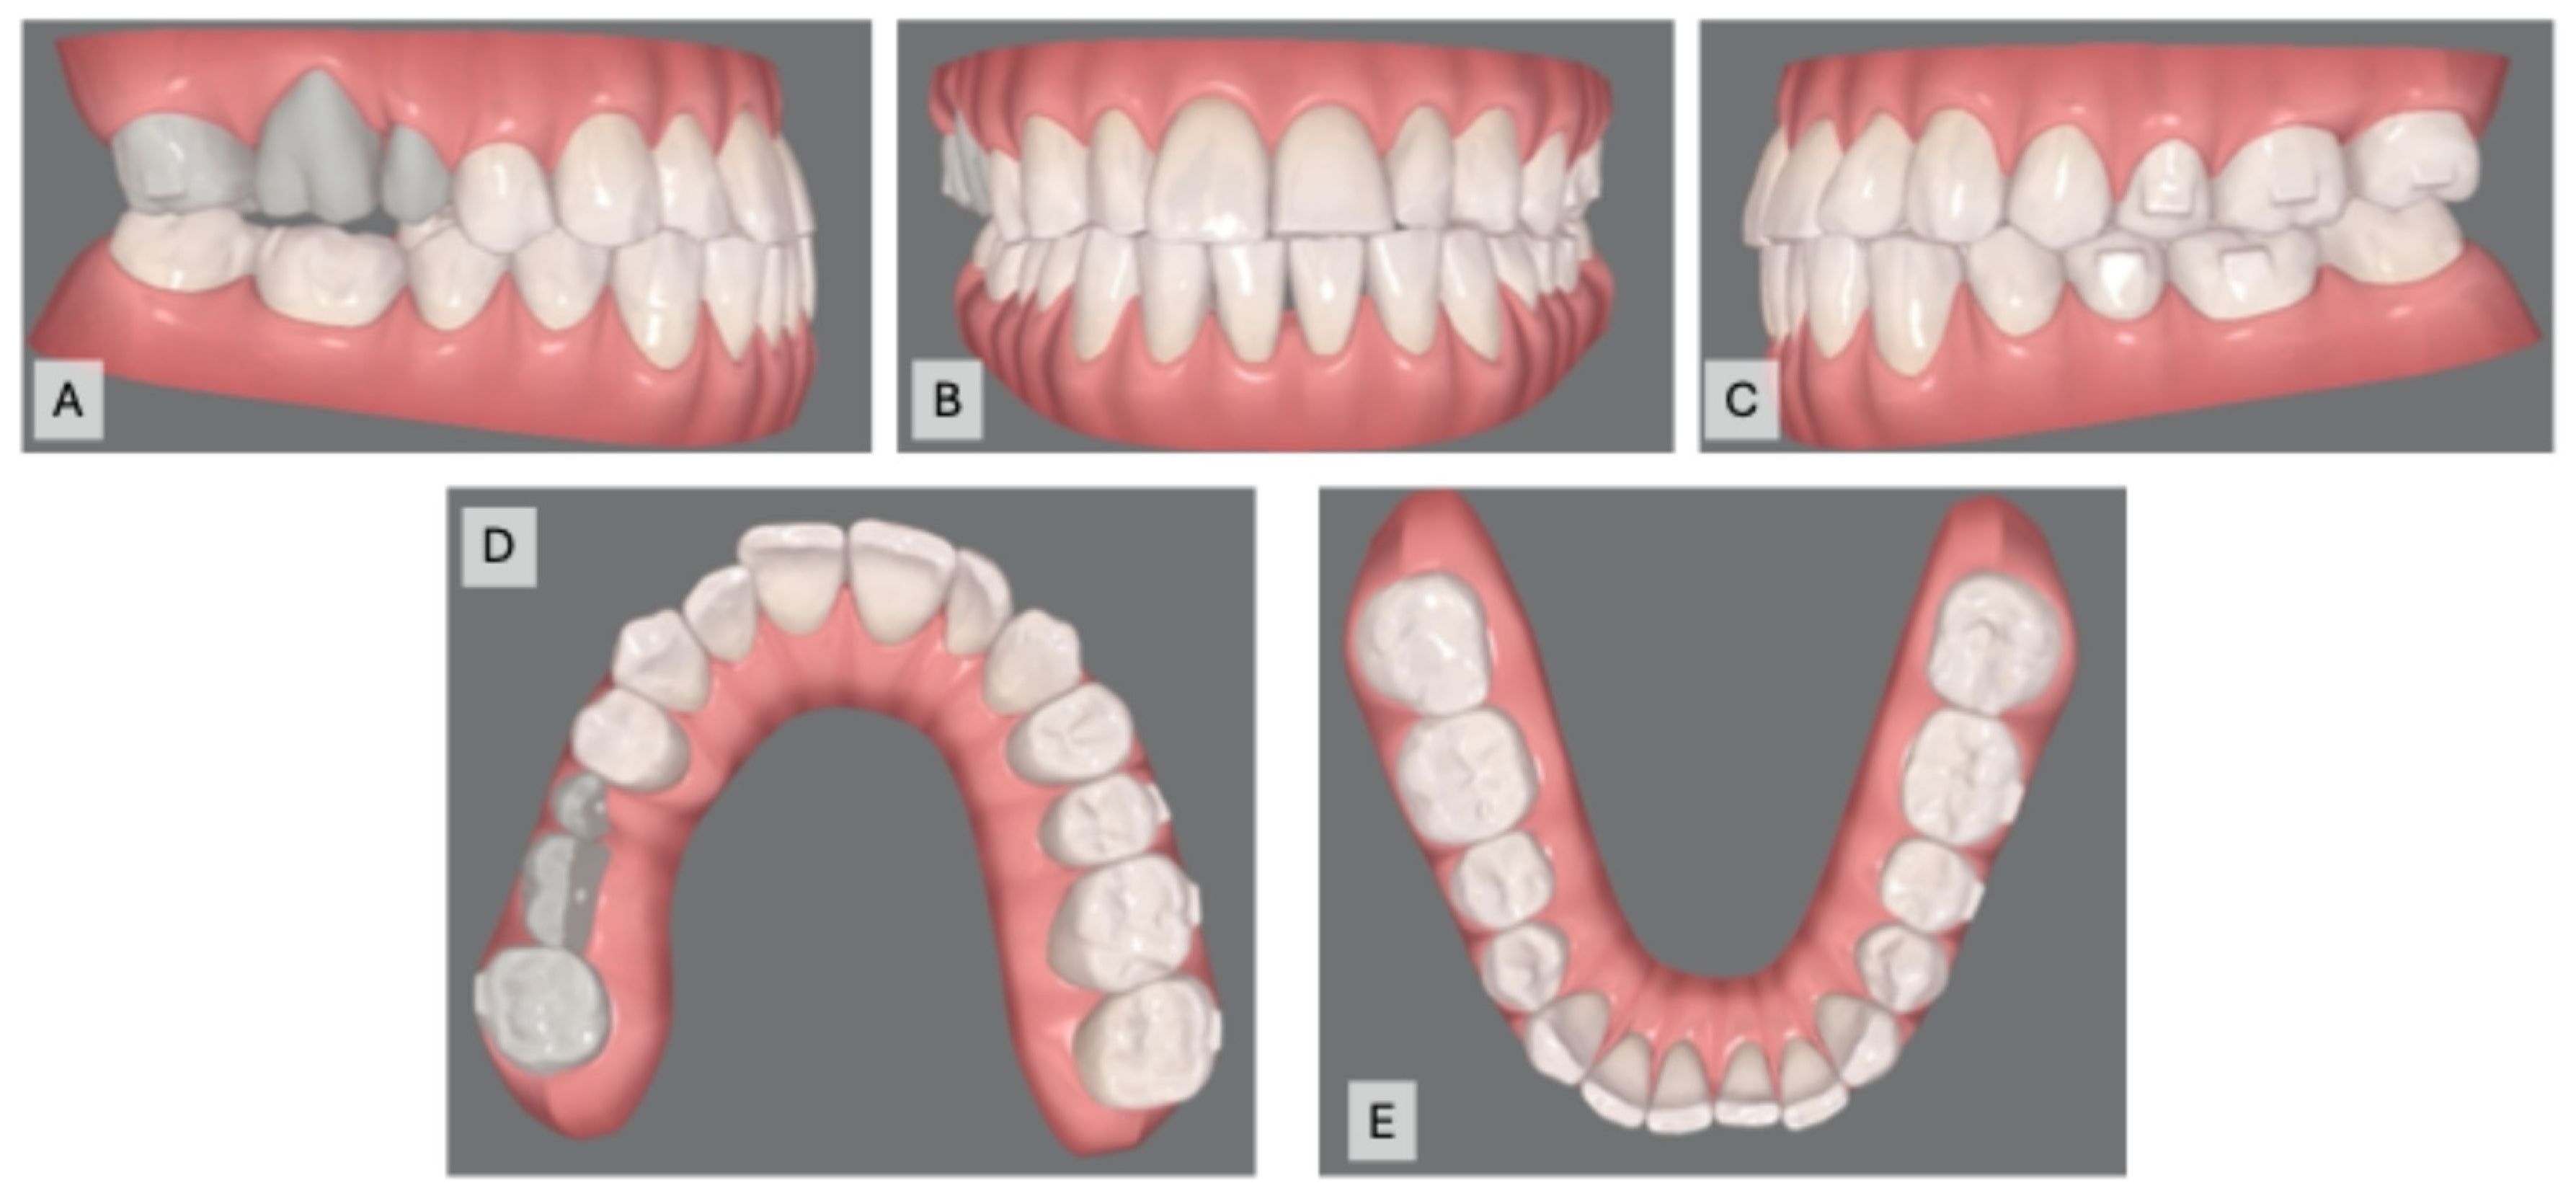

A 49-year-old Saudi female patient came to the orthodontic faculty clinics at Imam Abdulrahman bin Faisal University Dental Hospital with a complaint: “My teeth are crooked, and I would like to correct them”. Her medical history showed no significant findings. Her dental history showed multiple restorations and missing teeth. Upon clinical examination, multiple caries lesions, generalized calculus deposition, generalized gingival recession, a missing tooth (#3), two 3-unit FPDs on teeth #2, X, 4, & 13, X, 15, crowns on teeth #12, 19, 20, and 30, Class I malocclusion, an overjet range from 0 to 1 mm, a shallow overbite of 0–1 mm, a shifted lower midline of 1 mm, 3 mm upper crowding, and 1 mm lower crowding were found. The lateral cephalometric radiograph suggested a normodivergent pattern, with a Class III skeletal relation complicated by the retrognathic maxilla and proclined upper and lower incisors (Figure 1A–E and Figure 2A,B).

Figure 2.

Radiographs taken before orthodontic treatment: (A) orthopantomography (OPG) taken during the initial visit and (B) a lateral cephalometric radiograph before the start of treatment.

The orthodontic diagnosis was Class III malocclusion due to retrognathic maxilla complicated with mild lower crowding and reverse overjet.